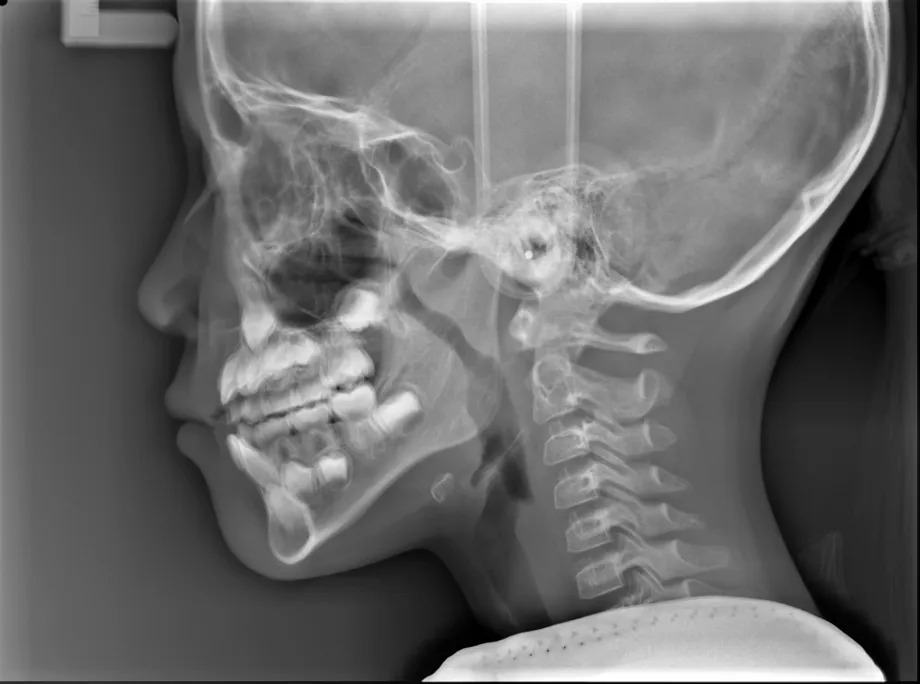

【治療前】

【治療開始から1年後】